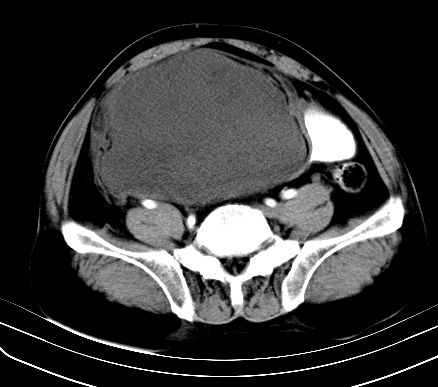

标题: CT19729B:男,74岁,因腿疼就诊,查体触腹部肿物,

增强扫描

动脉期

【ct表现】

1、肿块巨大,往往位于腹膜后,长大后才引起症状而就诊;那么位于腹膜后的肿瘤80%为恶性肿瘤。

2、实性肿瘤,增强扫描轻度不均强化,实性肿瘤一般不是好东西。

3、肿瘤边缘似见少许脂肪样密度。

4、腹膜后未见肿大淋巴结,但肿瘤于临近的肠管及组织接触紧密。

【诊断】

腹部占位,考虑位于腹膜后的恶性肿瘤,脂肪肉瘤(实体型)可能性大。

术后病理结果:腹膜后脂肪肉瘤。